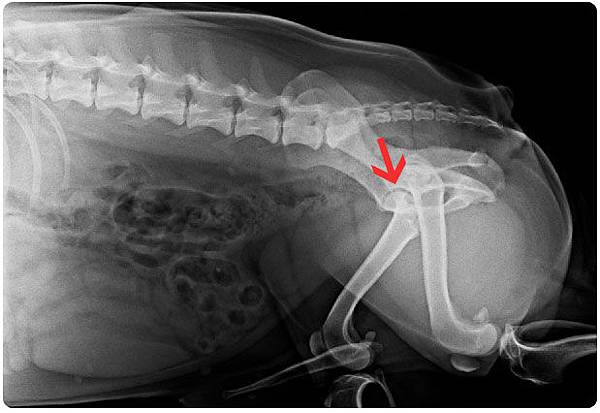

[島輝] 2011健檢@芸林